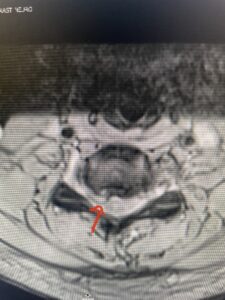

Fig: 2b Axial T2-weighted cervical MRI demonstrating spinal cord compression from C4-5 herniated disc (red arrow)